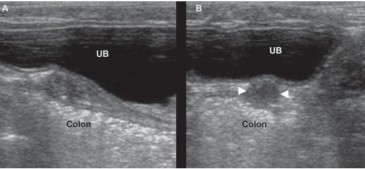

Hình 2.7. Tử cung ở một con chó lai 12 tuổi khỏe mạnh

Chú thích: A: Hình ảnh Sagittal. khối u cơ trơn cơ tử cung xuất hiện như một cấu trúc hình ống giữa bàng quang (UB) và đại tràng. B: Hình ảnh ngang. khối u cơ trơn cơ tử cung (giữa đầu mũi tên)

xuất hiện dưới dạng cấu trúc giảm âm tròn giữa UB và đại tràng.

Nguồn: Rachel Pollard & Silke Hecht (2015)